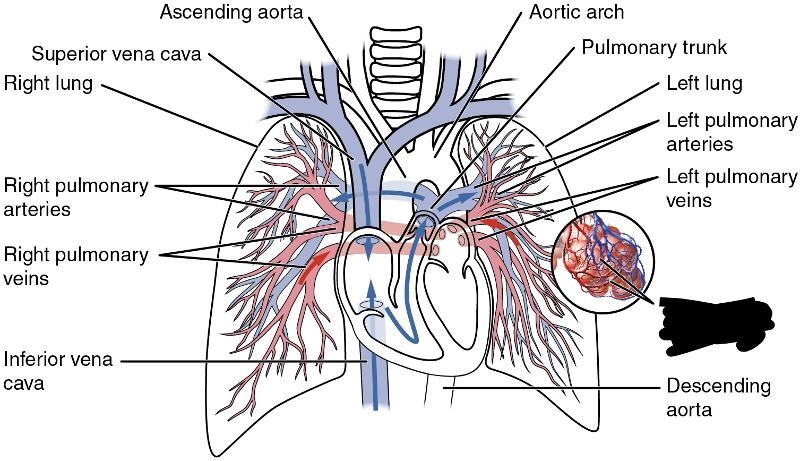

Aortic Arch

Ascending/descending aorta

left/right pulmonary artery/vein

Pulmonary trunk

Superior/inferior vena cava

Upper/middle/lower lobe (of lung)